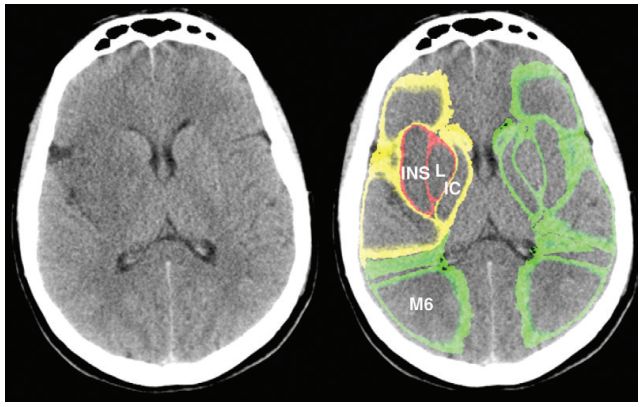

![]()

图2. 平扫CT图像无(左)和有(右)自动重叠分割ASPECTS区域,分割区域显示区域绘制和X射线衰减测量方法。根据制造商执行的任意截止值,颜色仅用于说明和显示与对侧相比,区域内X线衰减的差值。(绿色 =差值<1 HU; 黄色 = 1≤差值<3 HU;红色=差值>3 HU)。IC=内囊,INS=岛叶,L=豆状核,M6=M6区。